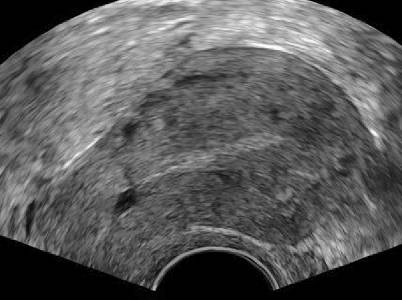

Abb. 4

Zystische Strukturen im Myometrium zeigen einen glatten Rand und im Farbdoppler keine Vaskularisation